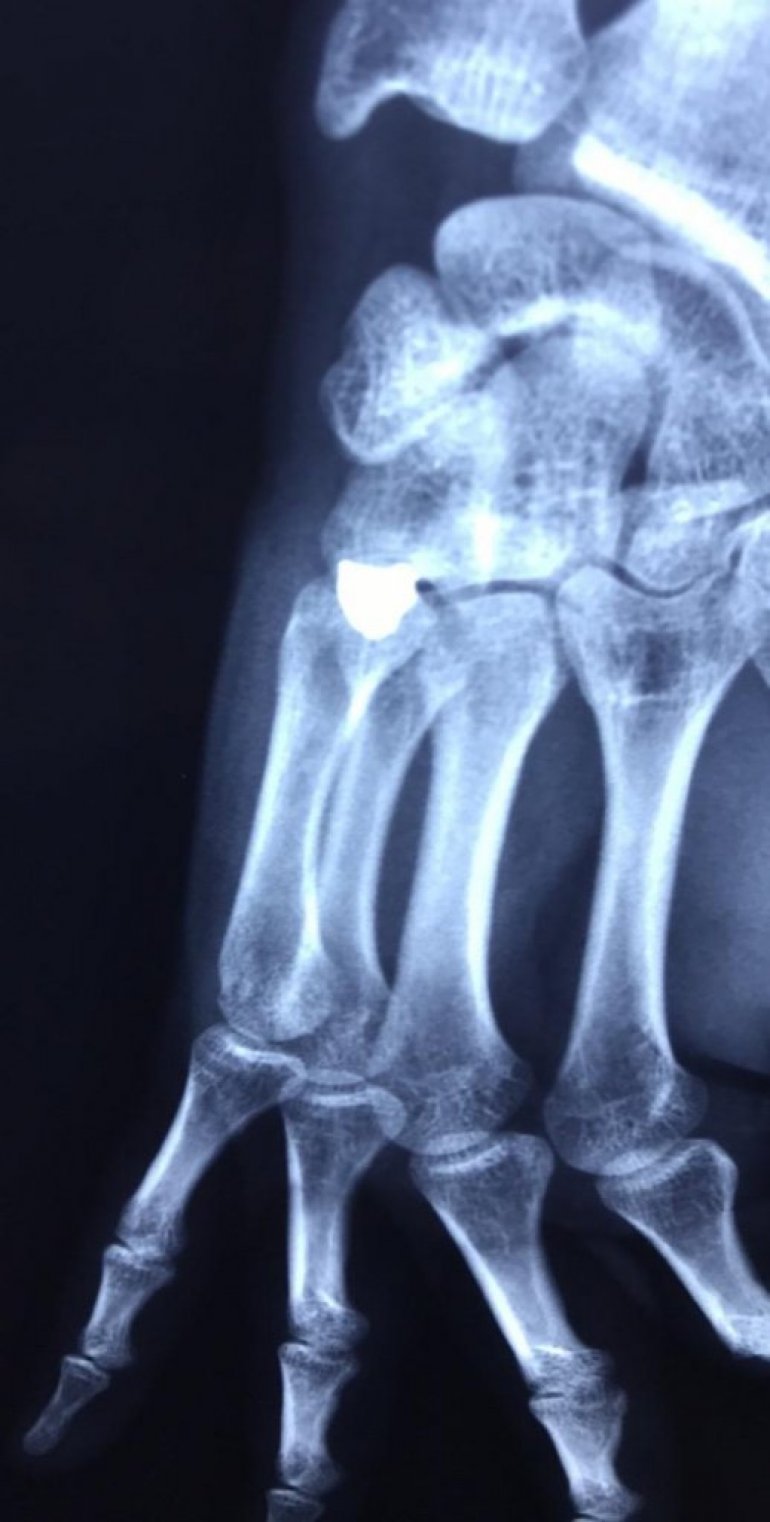

Погледајте и фотографије рентгентског снимка повређеног младића и фотографију метка којим је рањен Милош.

Фото: Новости